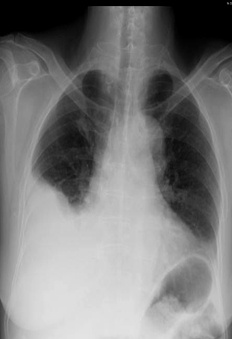

解题:片中可见肋膈角消失,根据公式得出胸腔积液